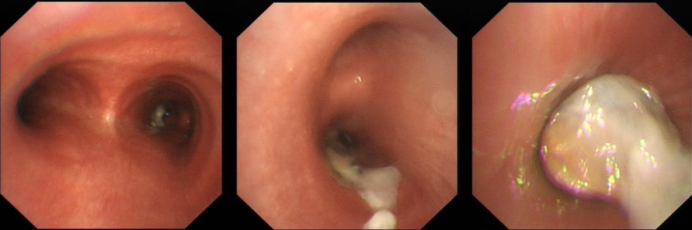

7  病例6支气管镜下所见

病例6:男性,21岁。主因“间断咳嗽、发热3个月”来我院治疗,伴间断右侧胸痛、夜间盗汗等。既往诊断1型糖尿病2年,血糖控制不佳,糖尿病酮症酸中毒,无外伤手术史,无烟酒嗜好。无家族疾病史。体格检查:一般好,双肺呼吸音清,右中肺野呼吸音稍低,未闻及干湿啰音。双下肢无水肿。T-SPOT-TB、G、GM试验均阴性;痰涂片、痰培养、BALF涂片培养均阴性。胸部CT显示肺部感染,右肺中叶实变;腹腔CT则可见坏死征象(图6)。支气管镜下观察到真菌生长形成新生物(图7),结合临床经验初步判断可能为毛霉感染。随后通过支气管镜介入技术取出该新生物(图8)。过程中引发出血,经抢救患者脱离危险。1周后复查CT,患者在未接受任何全身抗真菌治疗情况下,病灶缩小(图9)。需要注意的是,此类操作具有较大风险。